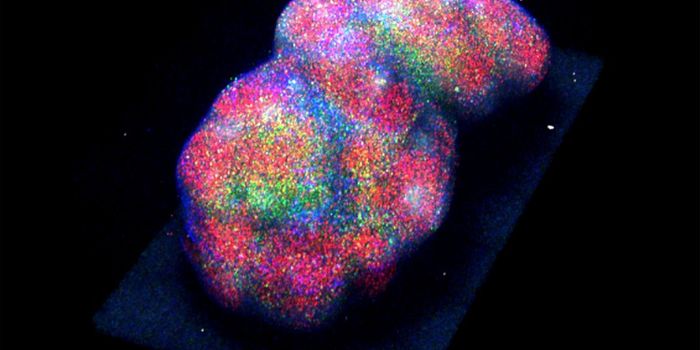

MAY 17, 2022CancerMuch has been written about scaling up cell culture for bioprocessing and other applications that require a very high de ...